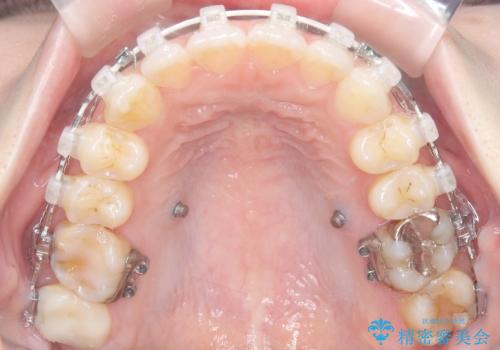

今回の矯正では、装置が目立たないよう透明なブラケットと白いワイヤーを使用。さらに、効率的な歯の移動のために、歯の裏側にリンガルアーチを設置しました。また、確実な奥歯の移動のために**TAD(矯正用アンカースクリュー)**を一時的に使用。これにより、犬歯を狙った位置へ正確に動かすことが可能に。目立ちにくい装置で快適に過ごしながら、理想的な歯並びと咬み合わせを獲得していただけました。